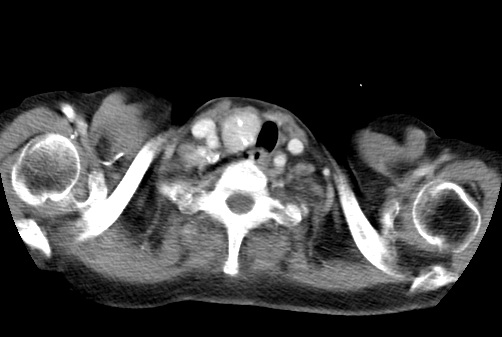

标题: CT23982:女67岁,胸部扫描时发现,甲状腺瘤? [打印本页]

标题: CT23982:女67岁,胸部扫描时发现,甲状腺瘤?

右侧甲状腺腺瘤!支持!不排除甲状腺癌可能!建议手术切除!

右侧甲状腺占位性病变,性质待定(甲状腺腺瘤?);建议:必要时行进一步检查。

右侧甲状腺占位性病变,性质待定(甲状腺腺瘤?);建议穿刺活检。

右侧甲状腺占位性病变,甲状腺腺瘤可能,建议穿刺活检。